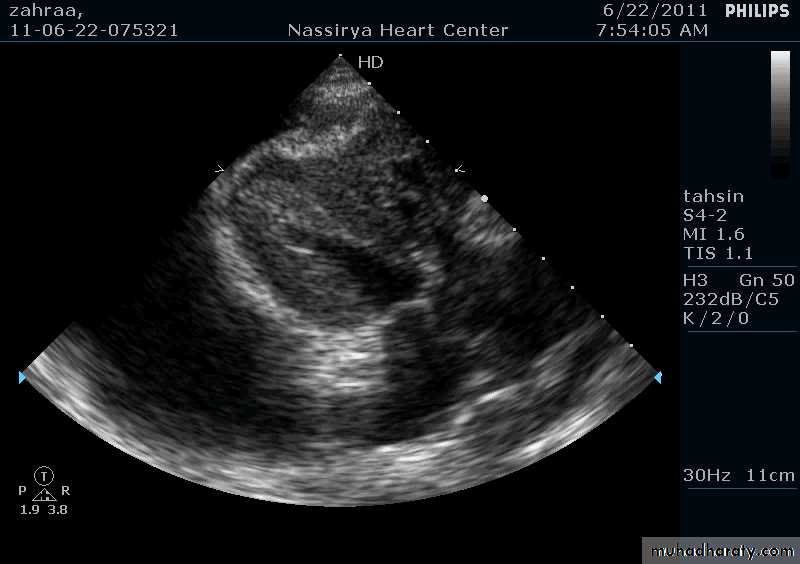

Pericardial Effusion: Investigation

Echocardiography: establishes the diagnosis31